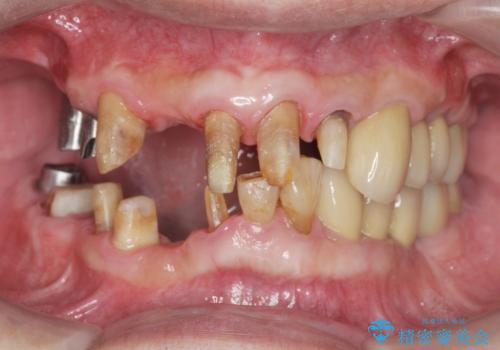

歯周病治療を伴う前歯審美セラミック治療

- 前歯の見た目をなんとかしたい、とセラミック治療を希望され来院されました。

セラミック治療を行う前に歯周病の問題を解決すべく歯周外科を行い歯周ポケットを除去し整備したのちセラミックブリッジ・クラウンの製作を行います。